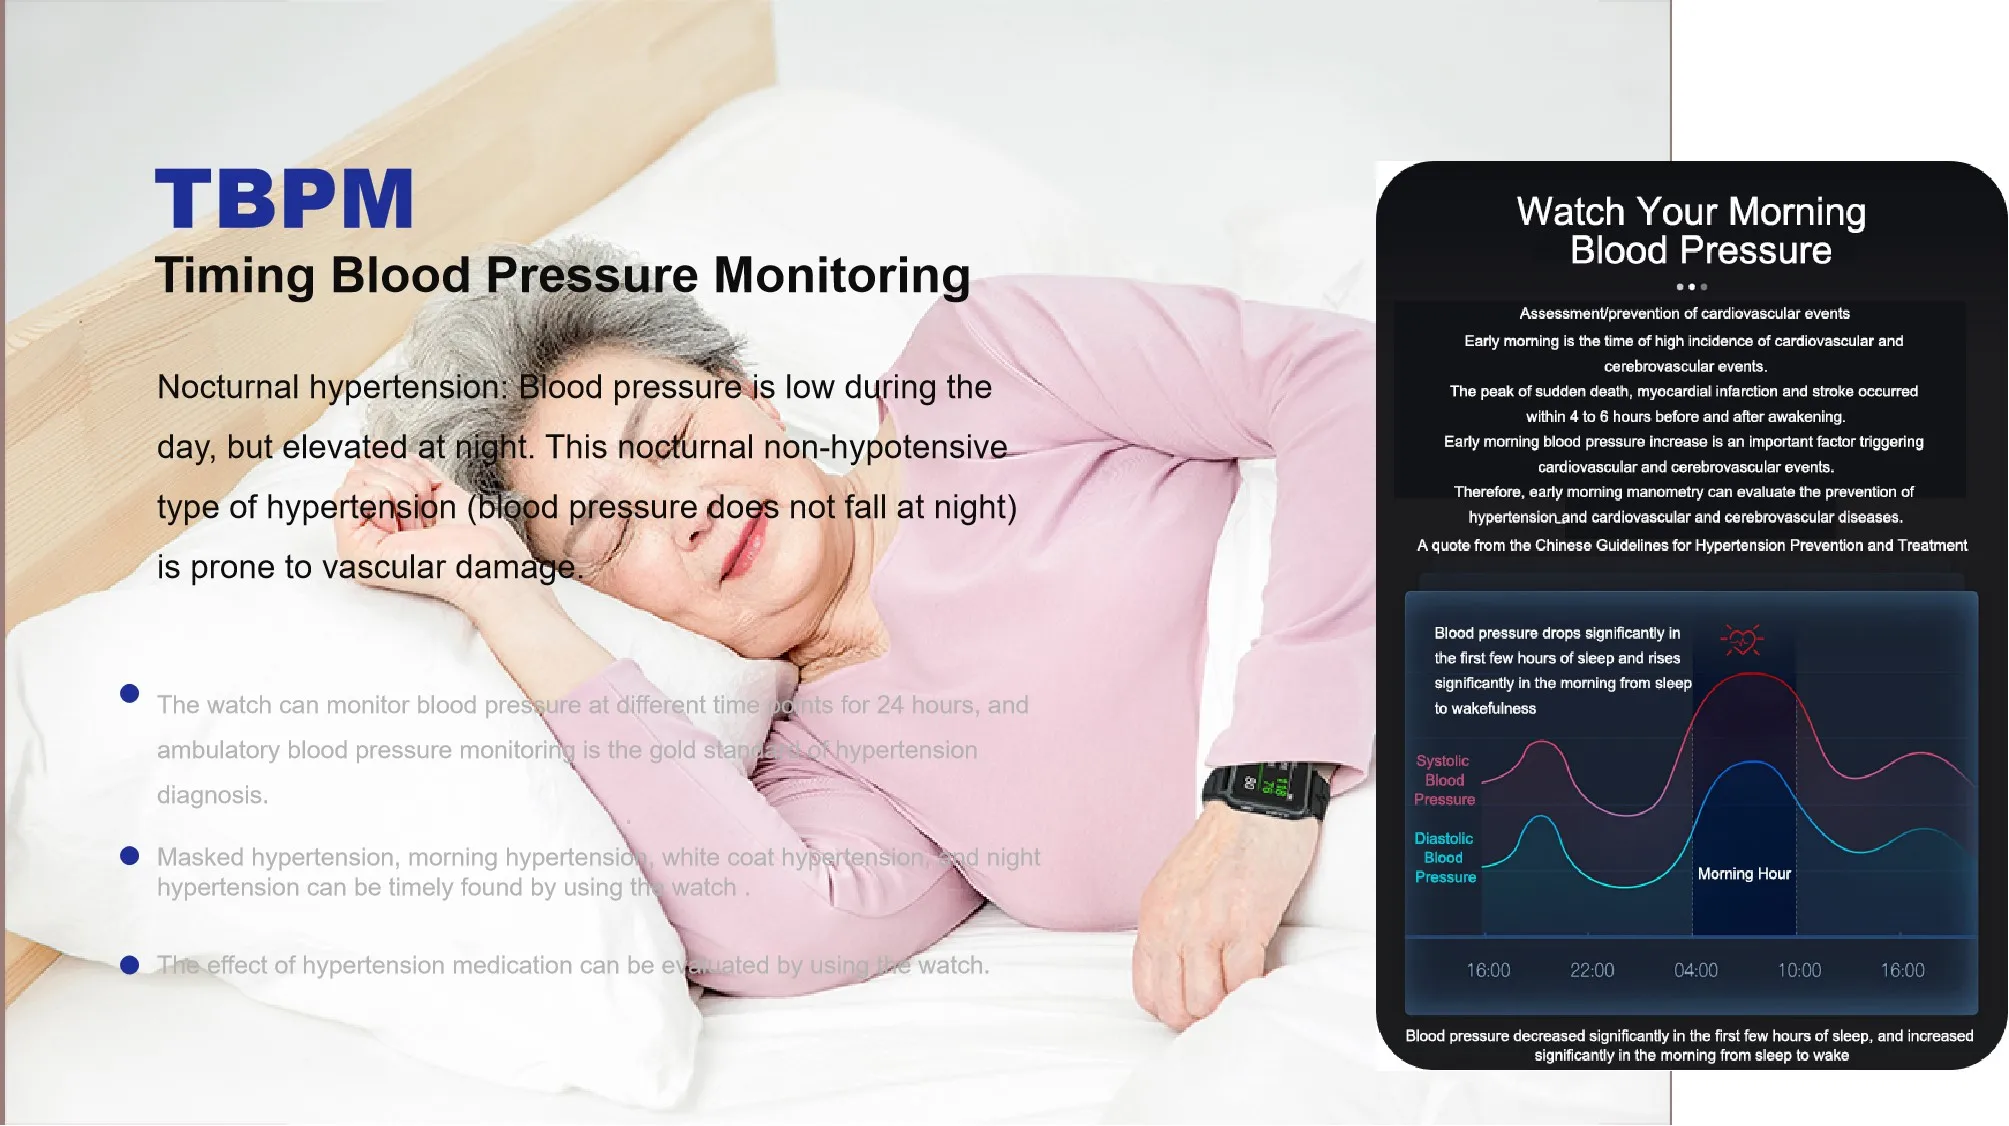

Application: Wrist

Bluetooth: Yes

Brand Name: komwell

Certification: CE

Choice: yes

Data Storage: Yes

Function: Blood pressure,ecg,Oximetry

Hign-concerned Chemical: None

Is Batteries Included: Yes

Item Type: blood pressure

Model Number: BPW1

Origin: China Mainland

System support: Bluetooth4.0 for iOS and Android

komwell Model: W1

languages: 17 languages can be freely converted

semi_Choice: yes

voice: Y